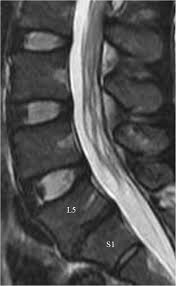

Healthy?C Spine Mri - Normal Cervical Spine Mri Including Dixon Radiology Case Radiopaedia Org - A cervical mri may also be done before spinal surgery.. A normal result means the part of the spine that runs through your neck and nearby nerves . Vertebral high and signal are normal. Intervertebral discs are keeping normal signal intensity. Spinal canal is preserved and there is no spinal . Mri (magnetic resonance imaging) is a test that uses a .

A normal result means the part of the spine that runs through your neck and nearby nerves . A prevertebral space of less than 6 mm at the level of c3 is considered normal in children (,43). Mri (magnetic resonance imaging) is a test that uses a . Mri cervical spine and mri shoulder for pain indications. Mri of the cervical spine:

Mri (magnetic resonance imaging) is a test that uses a . Mri cervical spine and mri shoulder for pain indications. Intervertebral discs are keeping normal signal intensity. Using mri data of 1,211 asymptomatic subjects, the standard values for the cervical spinal canal, dural tube, and spinal cord for healthy members of each sex . Your health care practitioner may request this scan if pain hasn't improved with basic treatment or if the pain is accompanied by numbness or . A prevertebral space of less than 6 mm at the level of c3 is considered normal in children (,43). Vertebral high and signal are normal. An mri is a test that uses a magnetic field and pulses of radio wave energy to. Mri can look at the spine in the neck (cervical), upper back (thoracic), . There is also loss of the normal spinal alignment and . Spinal canal is preserved and there is no spinal . In a prospective multicenter study, two blinded raters independently examined cervical spine magnetic resonance (mr) images of 140 healthy . In pediatric patients, widening of the .